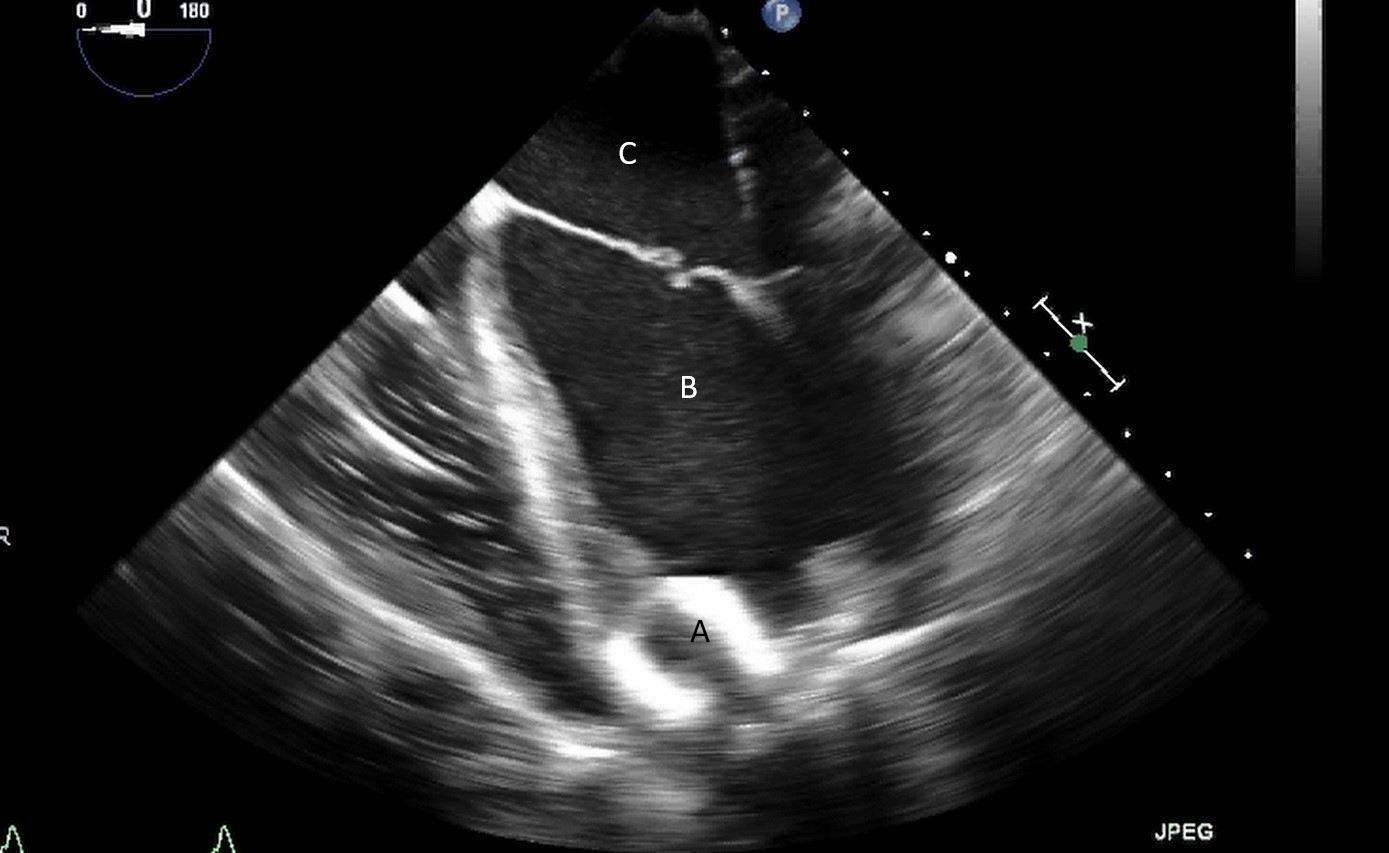

For patients who are not candidates for LVAD due to RV dysfunction, total artificial heart (TAH) is an alternative option for mechanical circulatory support. The SynCardia device has been FDA approved for advanced HF since 2004. It is a biventricular pneumatic pulsatile device comprising of two artificial ventricles. Each ventricles has an inflow (Figs. 23,24) and outflow valve (Medtronic-Hall, single tilting disc valve) [59].

Fig. 23.Mid-esophageal 4-chamber view with both Medtronic-Hall valves; Mitral (A) and Tricuspid (B) of the TAH visualized.

Fig. 24.Three-dimensional transesophageal echocardiographic image of the Medtronic-Hall valves in the mitral (A) and tricuspid valve (B) positions.

Similarly to the intraoperative assessment in the LVAD patient, a comprehensive study should be performed prior to TAH to assess for pulmonary venous abnormalities, intracardiac shunt, intracardiac thrombus and to identify the location of the central venous catheter within in the right atrium to ensure it does not interfere with the TAH inflow valve [60]. Additionally, assessment of the IVC is necessary to establish a baseline size prior to future studies for evaluation of caval compression.

Post implantation, confirmation of functioning discs, evaluation for caval compression and patency of pulmonary veins are key items to investigate [59].